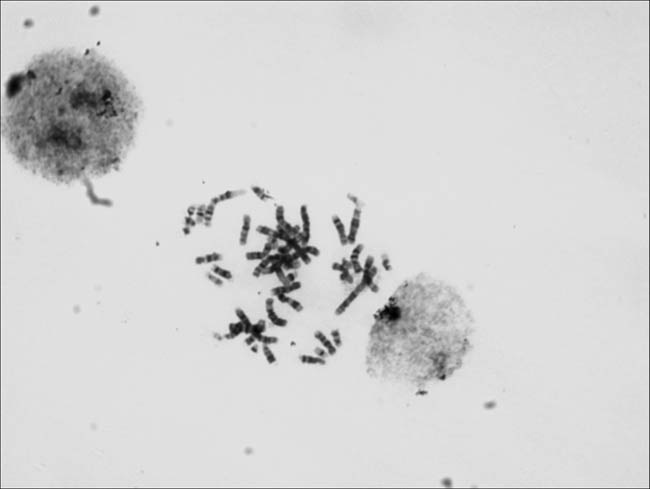

Should be the requirements of our customers, the Tucson special will be two high sensitivity CCD (TCC-1.4HICE (black and white) /TCC-1.4CHICE (color), in the biological study of microscopic images taken by chromosome released, welcome everyone to share.

Taken by TCC1.4CHICE

Taken by Tucsen TCC-1.4CHICE black and white pattern of color camera